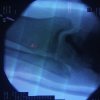

Una fractura de tobillo es la rotura de uno o más de los huesos del tobillo. Estas fracturas pueden ser:

Una fractura de tobillo es la rotura de uno o más de los huesos del tobillo. Estas fracturas pueden ser:

Cuando se necesita cirugía, es probable que esta implique el uso de clavijas de metal, tornillos o placas para sostener los huesos en su lugar mientras la fractura se consolida. Los elementos de soporte pueden ser temporales o permanentes.